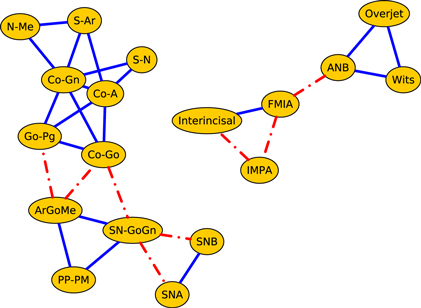

Figure 3 illustrates the correlation network of the cephalometric characteristics of the Class III patients (age 7–13 years) before orthopedic treatment with RME/FM (T1). We see that the network splits into two components: the dentoalveolar adaptive variables (figure 3, top) and the skeletal variables (figure 3, bottom). Moreover, the skeletal horizontal variables (figure 3, bottom right) and skeletal vertical variables (figure 3, bottom left) are loosely connected by a link among the gonial angle (ArGoMe) and the distance between Gonion and Pogonion points (Go-Pg).

Figure 3. Network analysis of cephalometric features of the Class III patients (T1, 7–13 years of age) before RME/facemask treatment. The dashed lines indicate negative correlations. In the upper part of the drawing are shown the dentoalveolar adaptive nodes that have been released from the rest of the network. The triangle formed by SN-GoGn, ArGoMe, and PP-PM variables comprises the parameters of maxillomandibular divergence. In the lower right part of the drawing is the sub-network of craniofacial skeletal features. The graphs shown here and in subsequent figures were produced using yEd Graph Editor by www.yworks.com.

Standard image High-resolution imageThe same patients were re-assessed at the end of the RME/FM therapy, followed by a second phase of treatment with fixed appliances (T2; figure 4). Network analysis show a more interlinked structure between skeletal and dentoalveolar adaptive nodes and the appearance of a strong correlation among the overbite and overjet variables.

Standard image High-resolution imageFinally, figure 5 illustrates the correlation network of the cephalometric characteristics of the cohort of the untreated Class III controls of 11–18 years of age (U2).

Standard image High-resolution imageWhile the network of treated patients at the end of RME/FM therapy showed a highly interconnected structure between dentoalveolar adaptive and skeletal variables (figure 4), the network of control patients exhibited two separate sub-networks pertaining to skeletal (left) and dentoalveolar (right) adaptive nodes (figure 5). The core of the network of treated patients consisted of a triangle composed by three maxillomandibular divergence variables: SN-GoGN, ArGoMe, and PP-MP. These variables seem to act as a bridge between skeletal features of Class III malocclusion and the dentoalveolar adaptive components of the craniofacial system.

We detect modules by applying the walktrap algorithm [42] on the complete graphs corresponding to consider all the possible edges weighted with their correlation rij; in particular, we use the igraph [44] implementation of the function walktrap.community of R [45]. To compare the results with the empirical outcomes of section 3.1, we show in all the pictures only links with a correlation correlation  and only nodes connected by such links. The analysis of the modules shows interesting differences among the three groups of patients: in fact, the modules characterising the networks of the patients before control (T1) and the untreated control patients (U2) share a similar structure (see figures 6 and 8) with three modules composed by analogous nodes. In fact, like in figure 3, the modules of T1 shown in figure 6 correspond to dentoalveolar adaptive nodes (top right of the picture), to skeletal horizontal nodes (bottom right of the picture) and skeletal vertical nodes (left of the picture); a similar correspondence exists among figures 5 and 8. Notice that for both T1 and U2 the modules are either separated or linked by negative links, indicating that such groups of nodes work as separate, non interacting, oro-facial modules. On the other hand, the network of treated patients (T2, figure 7) shows more modules ; apart to the new (respect to T1 and U2) isolated community formed by overjet and overbite (whose correlation is due to the successful action of the braces), the remaining communities are much more interlinked, possibly hinting a harmonization of the orofacial modules that start working together thanks to the orthodontic correction.

and only nodes connected by such links. The analysis of the modules shows interesting differences among the three groups of patients: in fact, the modules characterising the networks of the patients before control (T1) and the untreated control patients (U2) share a similar structure (see figures 6 and 8) with three modules composed by analogous nodes. In fact, like in figure 3, the modules of T1 shown in figure 6 correspond to dentoalveolar adaptive nodes (top right of the picture), to skeletal horizontal nodes (bottom right of the picture) and skeletal vertical nodes (left of the picture); a similar correspondence exists among figures 5 and 8. Notice that for both T1 and U2 the modules are either separated or linked by negative links, indicating that such groups of nodes work as separate, non interacting, oro-facial modules. On the other hand, the network of treated patients (T2, figure 7) shows more modules ; apart to the new (respect to T1 and U2) isolated community formed by overjet and overbite (whose correlation is due to the successful action of the braces), the remaining communities are much more interlinked, possibly hinting a harmonization of the orofacial modules that start working together thanks to the orthodontic correction.